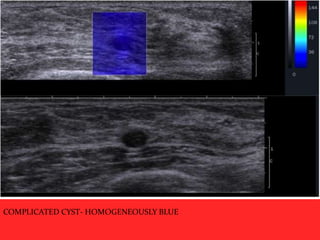

 Elastography has the potential to

differentiate complicated cysts form

solid masses.

 Shear-wave propagation does not occur

in cysts and therefore cysts should have

elastography values of zero and will

appear mostly black or homogeneously

blue on the color overlay elastogram

COMPLICATED CYST- HOMOGENEOUSLY BLUE